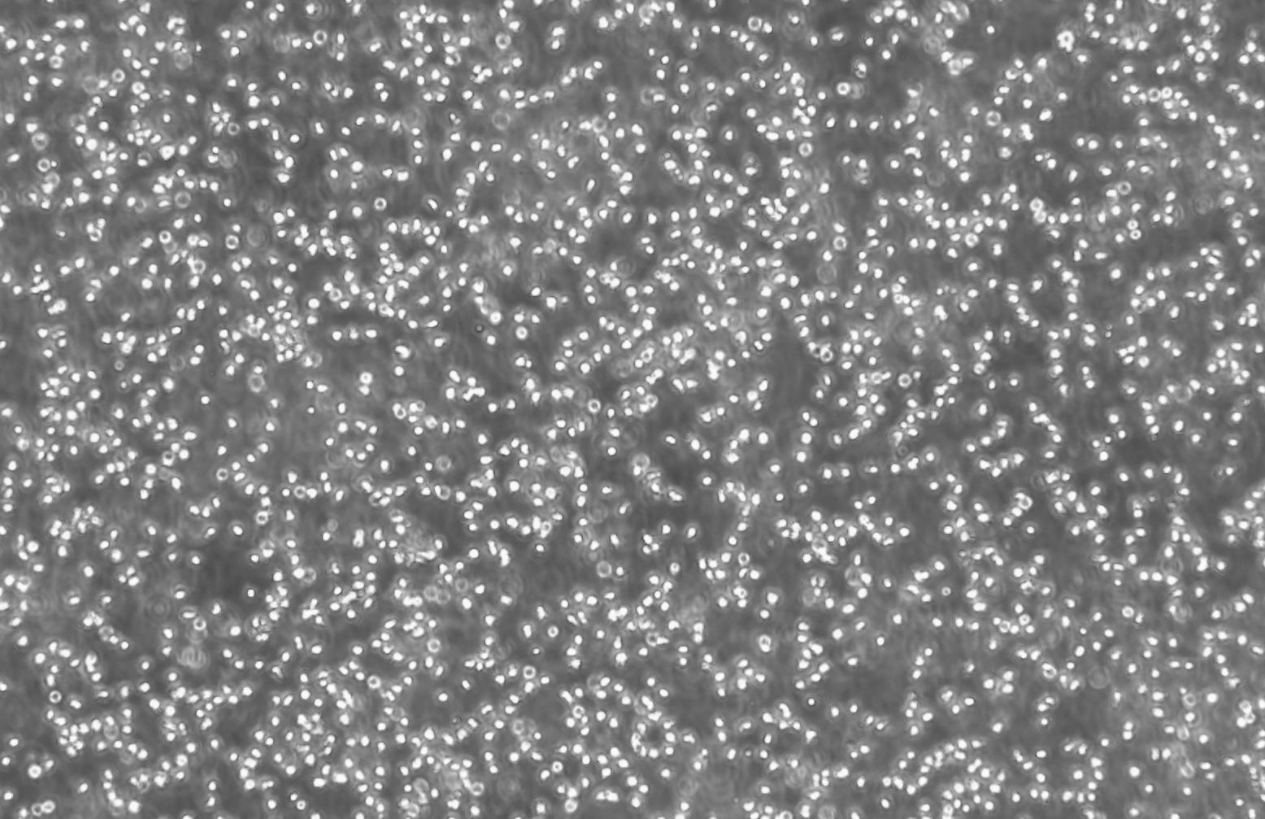

形態 |

圓形細胞 |

生長特征 |

懸浮生長 |